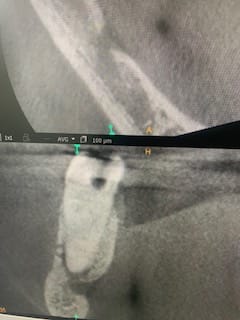

Wave one jaune en mésial, réciproc rouge distal, biocéramique et monocones.

Joli.

Mais avec une radio comme ça les très chers confrères de la SS me diraient qu'on ne voit pas les deux canaux mesiaux...

Avec l'image initiale je pense que je n'aurais pas tenté l'endo.

Bien joué.

ah , bien elle est très belle cette endo , tu vois quand tu veux :-)

Le wave one c’est gold et le reciproc c’est blue, eddy, ahplus bioceramique injectée directement dans le tiers apical, deux cones devant, un derrière.

Les canaux mesiaux étaient très très calcifiés, pas de risque pour le ndi.

Ça fait de jolies radios le ahplus !)